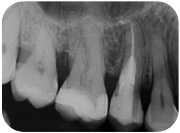

Sì, perchè ora faccio il figo, ma nel non lontano 2011, mi arriva una paziente con questo dente.

E questa è stata la mia reazione.

Cosa caspita era capitato a questo dente? Allarmato faccio vedere la radiografia a Federico, il mio socio, e anche lui pensa a qualcosa di brutto. Che so, un tumore di quelli incomprensibili che avevamo studiato solo sui libri di radiologia che si era insinuato all’interno di questo 4.6! ???

Quando nel 2013 mi è arrivato all’attenzione questo caso

Ho riconosciuto lo stesso fenomeno visto nella ragazza infestata da tessuti alieni di cui sopra e mi sono ricordato che all’università si era parlato di riassorbimenti esterni.

Si trattava di un riassorbimento esterno di classe IV.